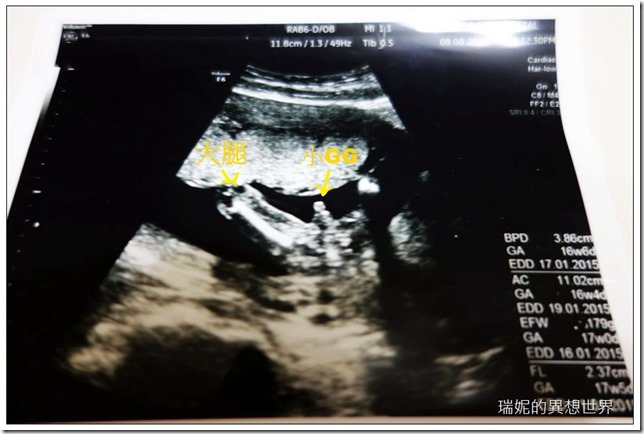

這一次的產檢,醫生已經十分確切地告訴我們二寶的性別,系低,二寶就是和安寶一樣都是男生。